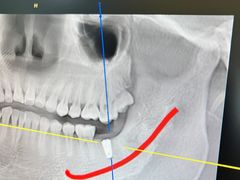

• 牙博士口腔品牌连锁(杨浦店)

• -牙博士口腔品牌连锁(杨浦店)